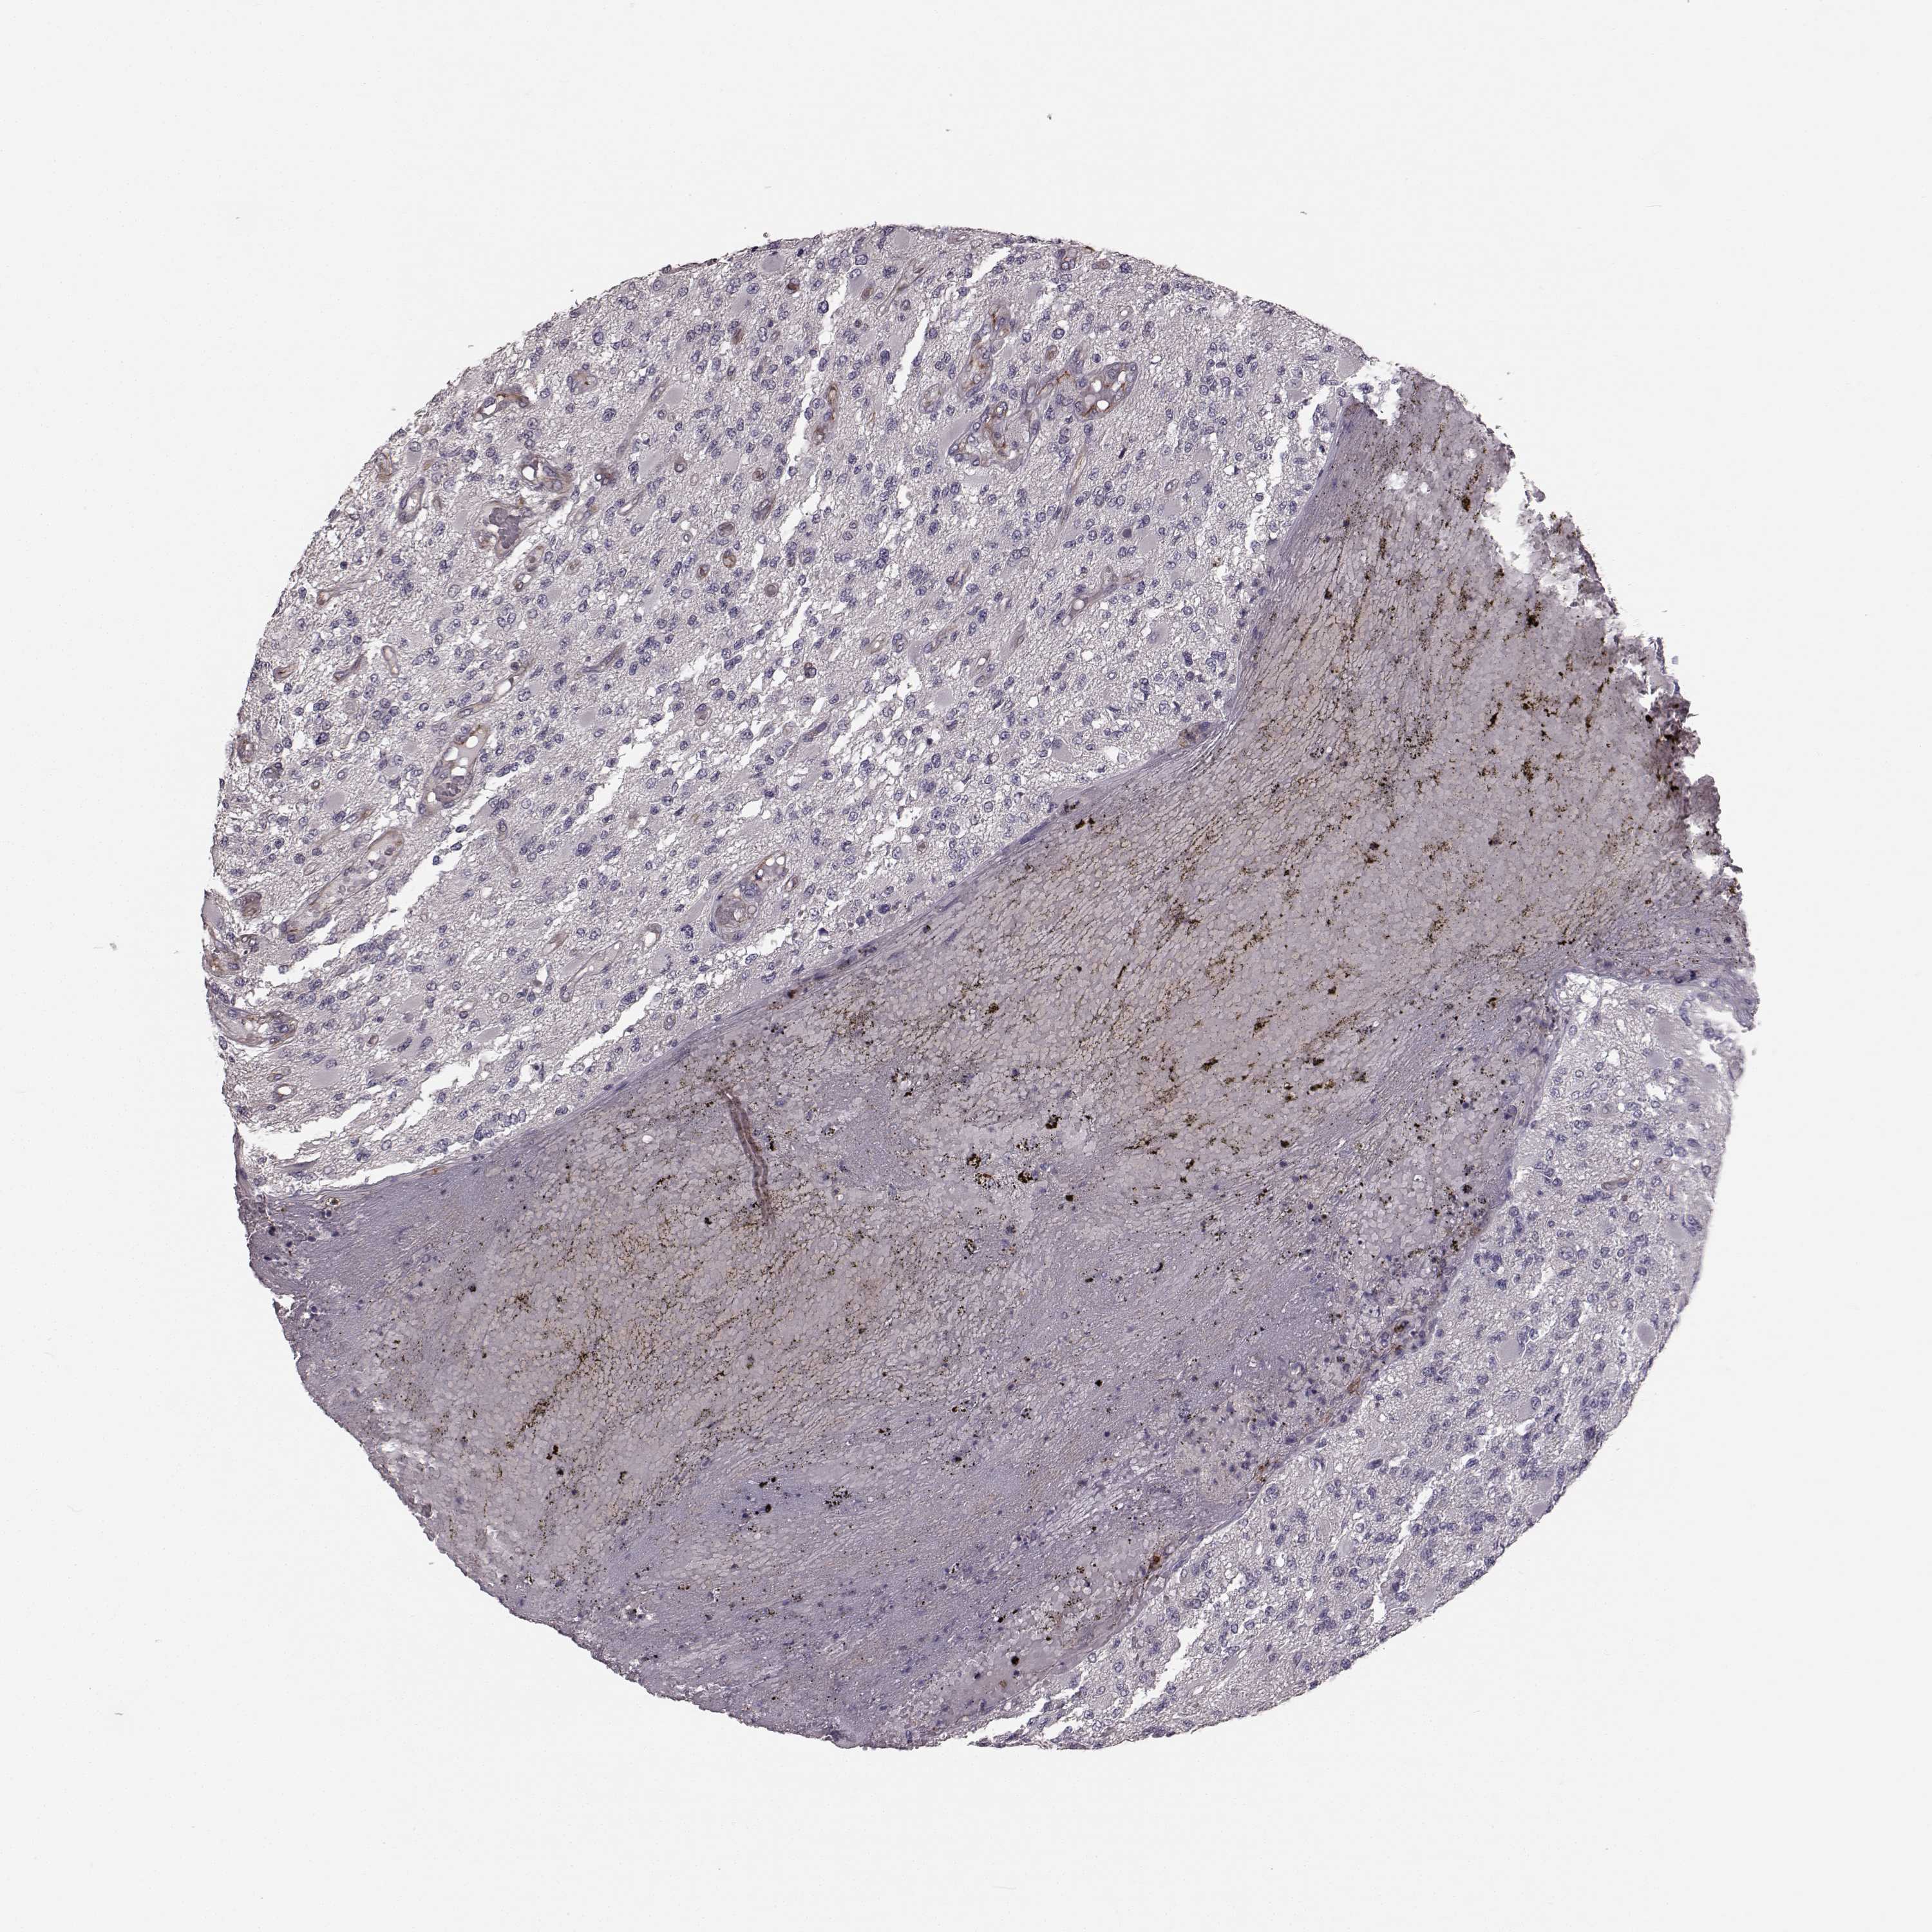

GLIOMA - Protein expressioni

A mouse-over function shows sample information and annotation data. Click on an image to view it in a full screen mode. Samples can be filtered based on level of antibody staining by selecting one or several of the following categories: high, medium, low and not detected. The assay and annotation is described here.

Note that samples used for immunohistochemistry by the Human Protein Atlas do not correspond to samples in the TCGA dataset.

Antibody stainingi

Antibody staining in the annotated cell types in the current human tissue is reported as not detected, low, medium, or high, based on conventional immunohistochemistry profiling in selected tissues. This score is based on the combination of the staining intensity and fraction of stained cells.

Each image is clickable and will lead to virtual microscopy that enables deeper exploration of all samples and also displays staining intensity scores, fraction scores and subcellular localization as well as patient and tissue information for each sample.

Antibody HPA067812

Antibody HPA071461

Staining

High

Medium

Low

Not detected

Intensity

Strong

Moderate

Weak

Negative

Quantity

>75%

75%-25%

<25%

None

Location

Nuclear

Cytoplasmic/membranous

Cytoplasmic/membranous,nuclear

Glioma, malignant, Low grade

Glioma, malignant, High grade